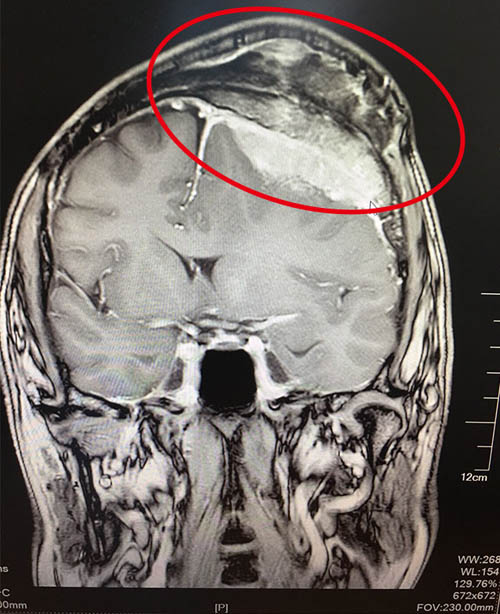

好景不长,两年前的夏天,王先生突然莫名的头晕,他以为是天气热,干活劳累所致,就没当回事。没想到在今年7月份,头晕加重,发作频繁,不能忍受。家人随即劝说王先生,将他送到当地医院,做CT检查显示:颅内占位性病变,医生说情况有些严重,需要转院。怀着忧心忡忡的心情,王先生在上海某三甲医院做了核磁共振检查,结果让人震惊:左额凸面占位伴颅骨及皮下侵犯,考虑间变血管外皮瘤,也有可能是淋巴瘤。医生说由于肿瘤巨大,性质难以确定,术后可能出现偏瘫、失语等并发症,手术难度高,风险大,建议他们转到其他医院进行治疗。听医生这么说,王先生和家人才感到危机四伏。

术前核磁显示:左侧额部(大脑凸面)侵袭性脑瘤,侵及颅骨和软组织